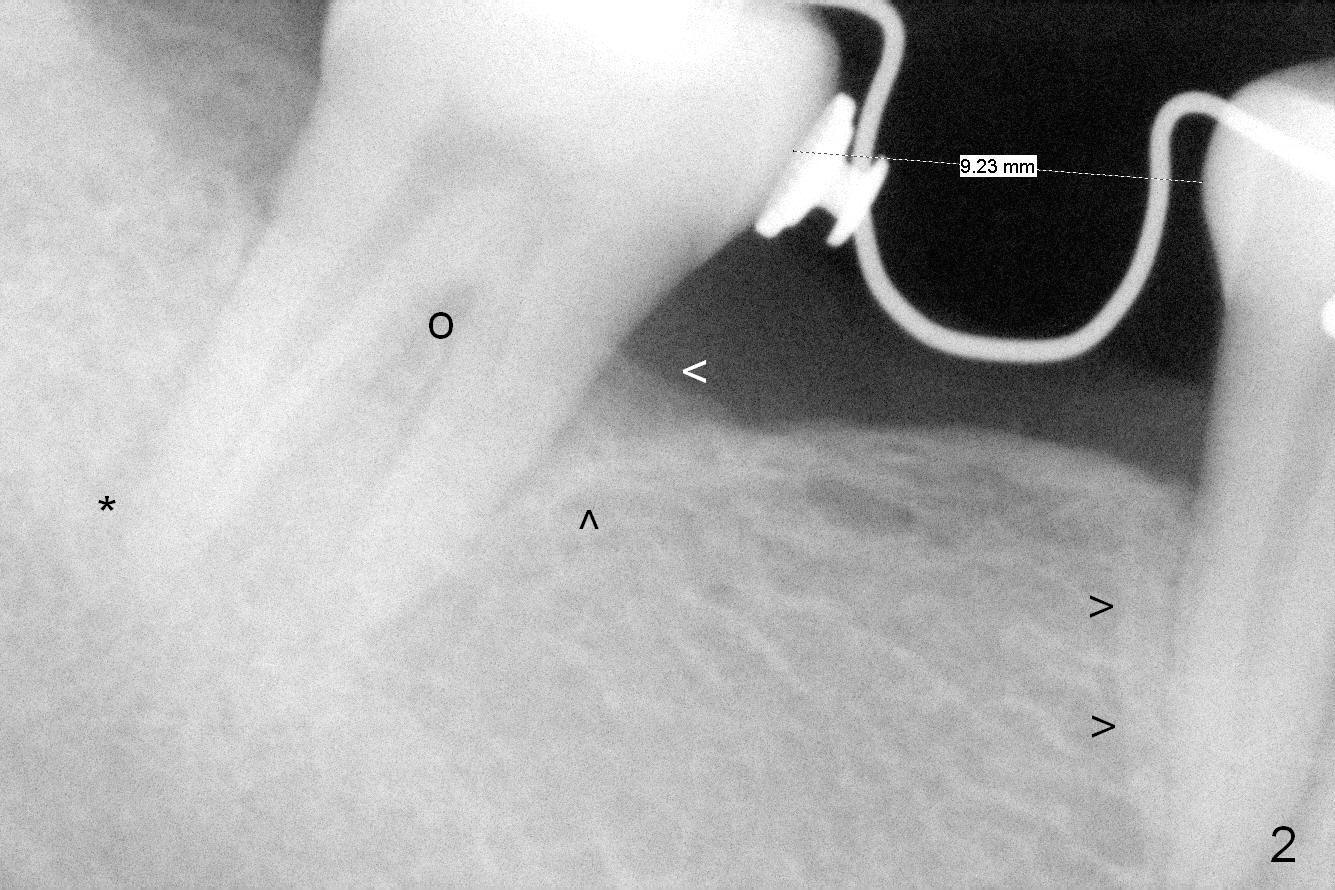

Six months of orthodontic uprighting (including open coil spring, Omega loop and lingual buttons), there seems to be enough space to place an implant at #30 with new bone formation mesial to #31 and distal to #29 (Fig.2,3 arrowheads). The center of resistance (for rotation) is at the furca (Fig.2 O). The void (*) created with upright is going to be filled.